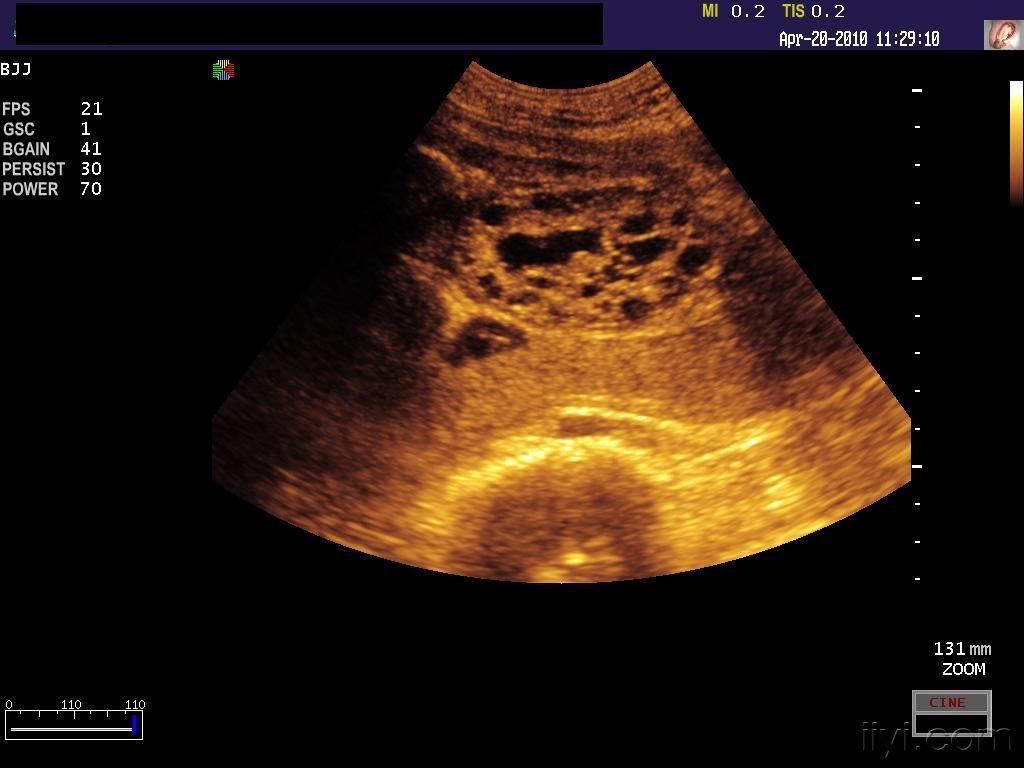

多囊肾最直接的诊断就是影像学,做个肾彩超,ct一目了然.

胎儿左肾多囊性改变?

胎左侧多囊肾右肾积水